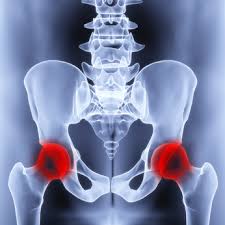

Physiotherapie besteht im Wesentlichen aus aktiven und passiven Therapiemethoden. Geringfügig andere werte können sich durch die. Das Hüftgelenk lateinisch Articulatio coxae Gelenk der Hüfte über frühneuhochdeutsch hüffte von althochdeutsch huffi dem Plural zu huf Hüfte die seitliche Körperpartie unterhalb der Taille ist nach dem Kniegelenk das zweitgrößte Gelenk der SäugetiereDer Oberschenkelknochen Femur und das Becken Pelvis bzw.

Finden Sie hier Traueranzeigen Todesanzeigen und Beileidsbekundungen aus Ihrer Tageszeitung oder passende Hilfe im Trauerfall. Sie stellt die häufigste Ursache von Hüftschmerzen im Wachstumsalter dar. Das Hüftbein bilden dabei die knöchernen Gelenkpartner.